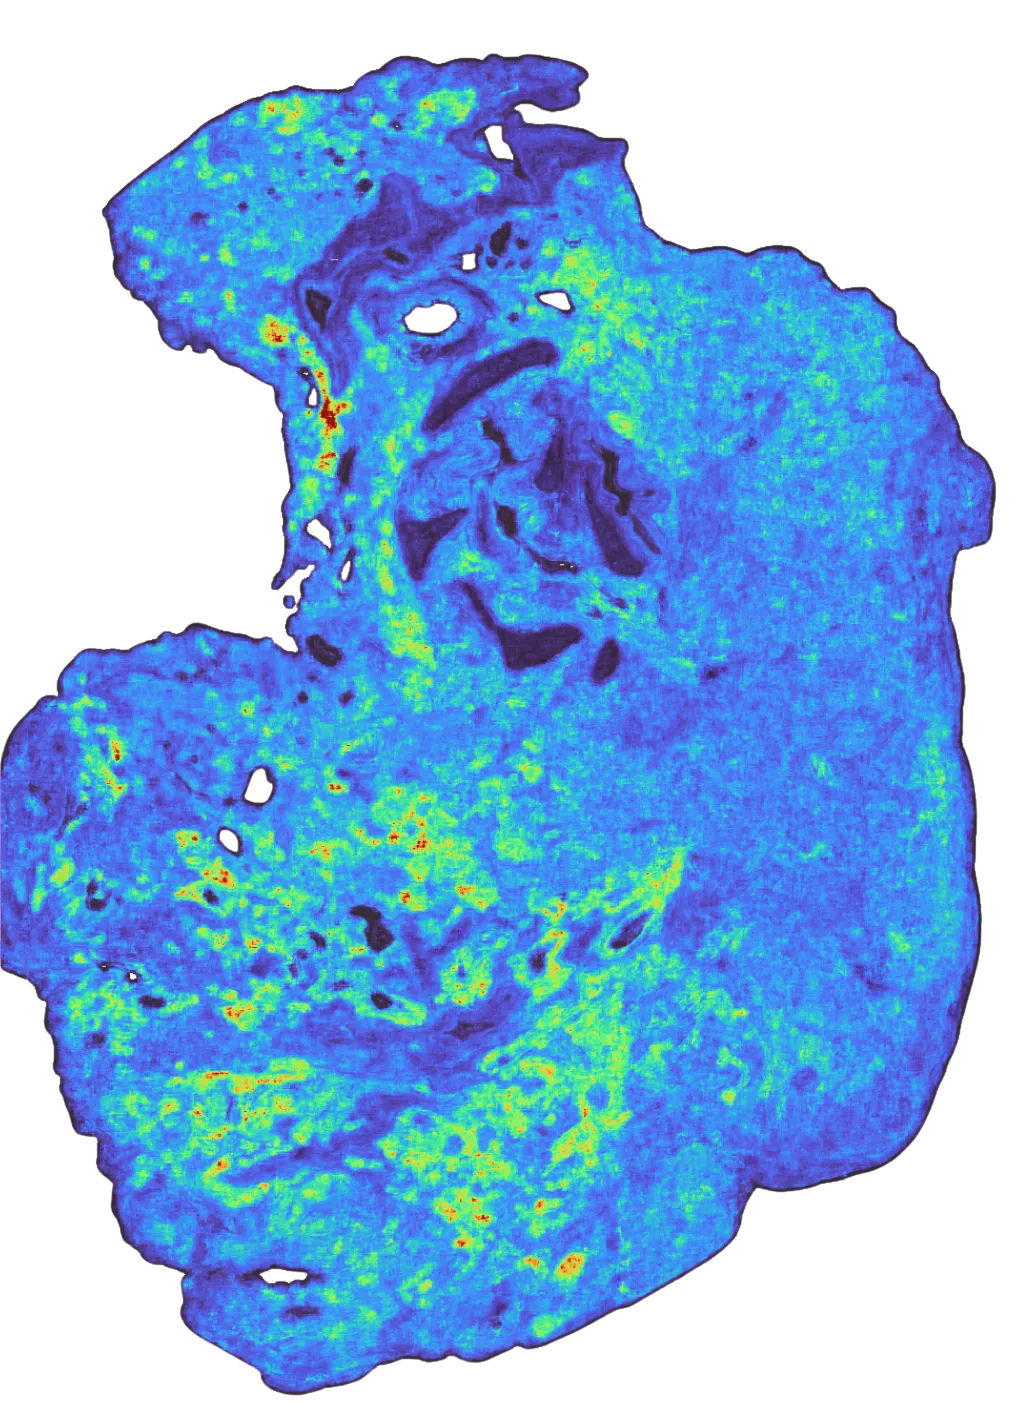

To give a visualization on what model predictions look like: on the left, we see the raw RNA abundance of this gene in a single tumor sample (in yellow), in the middle, the binned values of those ground-truth transcripts, and on the right, the model’s predictions (yellow is high, purple is low) when given only the H&E of that sample. You can see that while the grids are larger than any individual cell, in aggregate, the general spatial pattern they make up closely matches the ground truth.

Because it’s hard to grok what a spatial correlation of 0.5 means versus a correlation of 0.2, some examples of (sample x gene) pairs at different levels of spatial correlation are shown below.

In the cases where a firmly delineated spatial pattern exists in the data, TARIO-2 can recover it, often achieving correlations far above the averages presented in Figure 2. As the transcriptomic pattern grows sparser or more diffuse—the pattern that most genes have—TARIO-2 predictions decline in accuracy, but in those cases the absolute spatial pattern matters less than the bulk values.

This said: it’s worth pointing out that even predictions that correlate only weakly with ground truth can be biologically meaningful. For example, the rightmost prediction in Fig 3 has a correlation of 0.17 but is far from random: some spatial patterns in the H&E are at least suggestive of higher or lower gene expression levels, even though the measured expression is sparse and noisy (possibly due to false negatives in the SpT assay itself). So although some genes are much harder to predict than others, they nevertheless provide a meaningful training signal that TARIO-2 can use to infer the overall biology of the tissue.